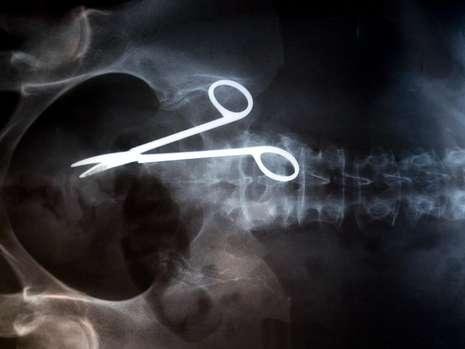

Schere im Patienten vergessen

Datum: 03.12.2009